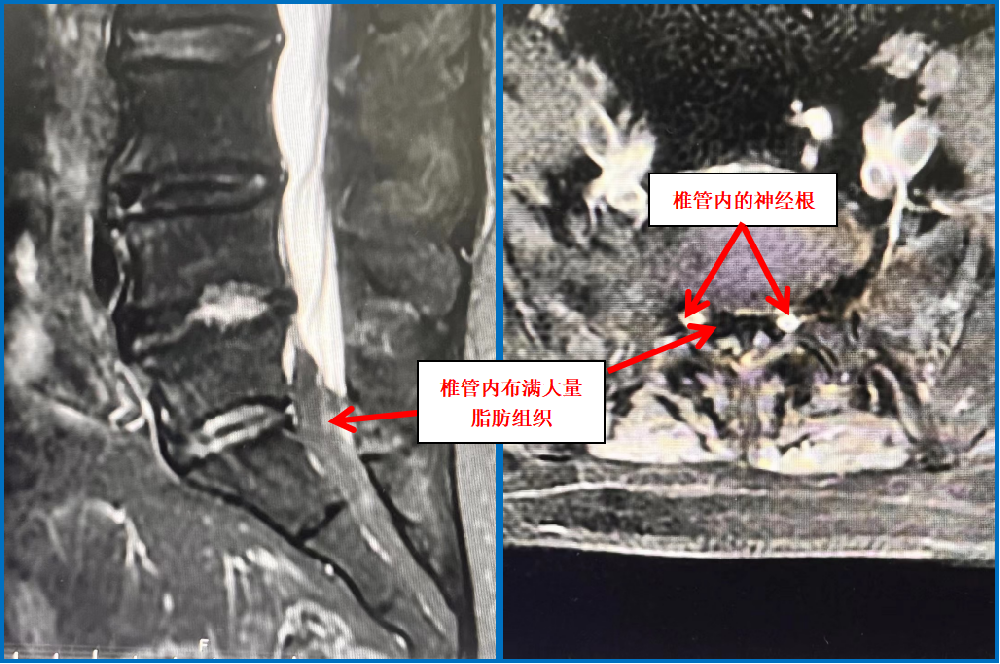

患者經(jīng)他人介紹來到我院脊柱外科門診就診,朱中蛟副主任通過患者的主訴及詳細的查體發(fā)現(xiàn)她存在間歇性跛行的表現(xiàn),腰椎過伸試驗陽性,提示為典型的腰椎管狹窄的臨床表現(xiàn),但通過患者的腰椎CT,卻發(fā)現(xiàn)其不存在腰椎間盤突出或黃韌帶肥厚、骨性增生等情況,不存在腰椎管狹窄。但患者癥狀這么重,肯定有問題!細心的朱中蛟醫(yī)師建議患者完善核磁共振等檢查,發(fā)現(xiàn)她的椎管內(nèi)擠滿了脂肪,導致硬膜囊受壓變形成Y型。

原來,這是一種比較罕見的“特發(fā)性椎管內(nèi)硬膜外脂肪增多癥”。硬膜外脂肪增多癥(Spinal epidural lipomatosis, SLE)是指椎管內(nèi)硬膜外間隙正常脂肪組織的病理性增生。其原因是椎管內(nèi)脂肪填充,行走時黃韌帶皺褶,椎管內(nèi)靜脈充血導致椎管進一步狹窄,壓迫了馬尾及神經(jīng)根所致。好發(fā)于男性,好發(fā)于胸段,其次為腰段。硬膜外脂肪增多癥常見的病因多與長期攝入外源性甾體類激素、激素異常疾病、肥胖癥等有關。

正常人的椎管內(nèi),都含有少量的脂肪組織。但該患者的腰椎管內(nèi)脂肪含量卻異常增多,對神經(jīng)產(chǎn)生了明顯的壓迫,因而出現(xiàn)相應的神經(jīng)壓迫癥狀,嚴重影響了工作和生活,需要手術治療。但常規(guī)開放手術創(chuàng)傷大,并且患者體型肥胖,對手術暴露及切口愈合都有一定影響。朱中蛟帶領科室團隊經(jīng)過認真檢查、準備,并與患者溝通后,決定通過UBE(單側雙通道脊柱內(nèi)鏡技術)手術為患者解除病痛。